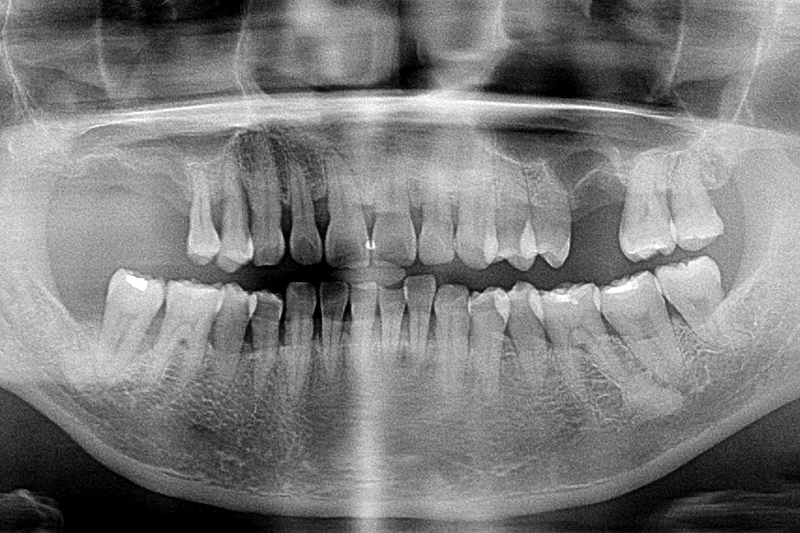

缺牙多顆-全口X光攝影

案例一

術前